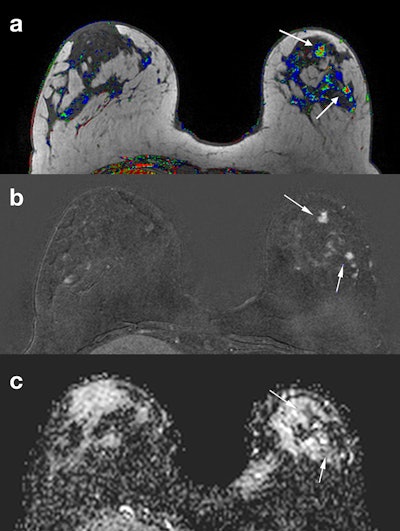

Same patient as in previous figure. Corresponding slices from (a) DCE postcontrast image, (b) DCE subtraction image, (c) ADC map. Two BI-RADS 4 lesions (arrows) were identified in a different quadrant from the index tumor. ADC characterized them as malignant (ADC = 1.28 x 10-3 mm2/sec). An MR-guided vacuum-assisted biopsy was performed in the largest of the two lesions, and an additional multicentric invasive ductal cancer was confirmed.Same patient as in previous figure. Corresponding slices from (a) DCE postcontrast image, (b) DCE subtraction image, (c) ADC map. Two BI-RADS 4 lesions (arrows) were identified in a different quadrant from the index tumor. ADC characterized them as malignant (ADC = 1.28 x 10-3 mm2/sec). An MR-guided vacuum-assisted biopsy was performed in the largest of the two lesions, and an additional multicentric invasive ductal cancer was confirmed.